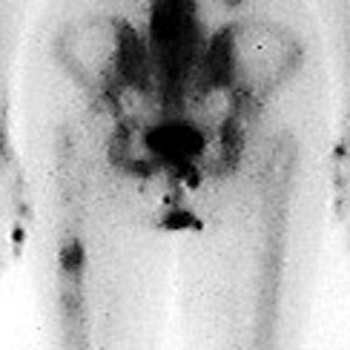

FRACTURES

STRESS OR INSUFFICIENCY

Left pubic bone

Left inferior pubic ramus